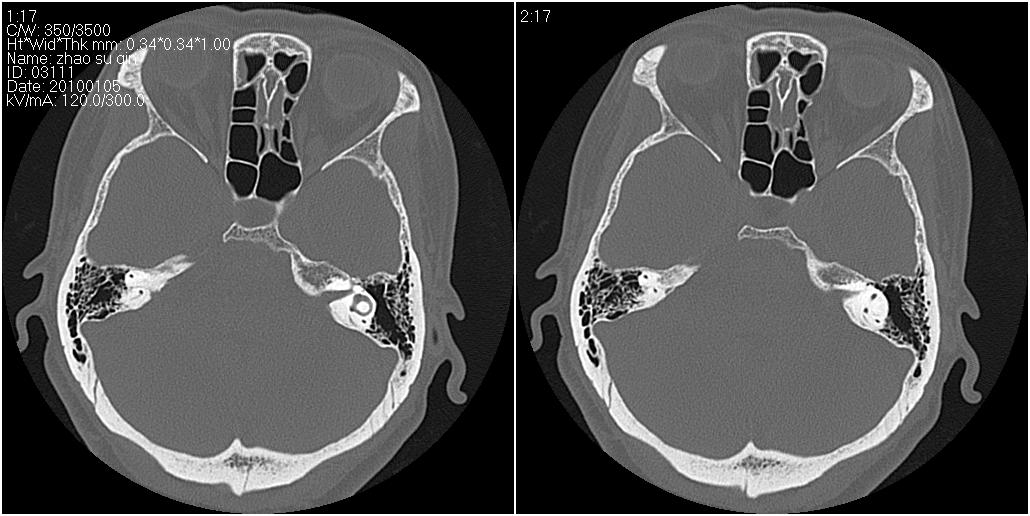

标题: CT24015:一个头部外伤患者进行鉴定,除了左侧筛板骨折,哪 [打印本页]

标题: CT24015:一个头部外伤患者进行鉴定,除了左侧筛板骨折,哪

1)左侧筛板骨折。2)双侧筛窦炎症(或积血)。

请明示骨折部位。